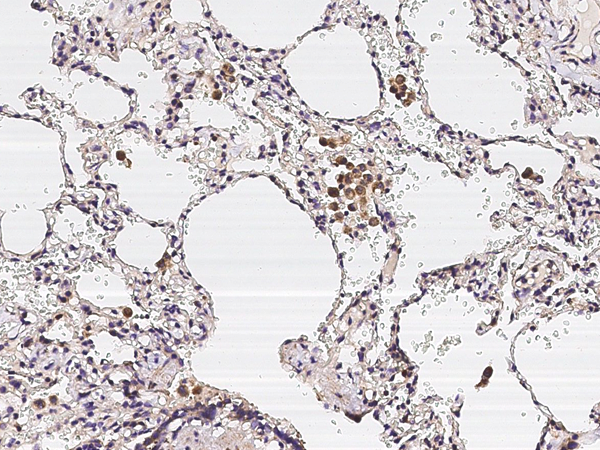

IHC (Immunohistochemistry)

(Immunochemical staining of human IL1R7 in human lung with rabbit polyclonal antibody (1:5000, formalin-fixed paraffin embedded sections).)